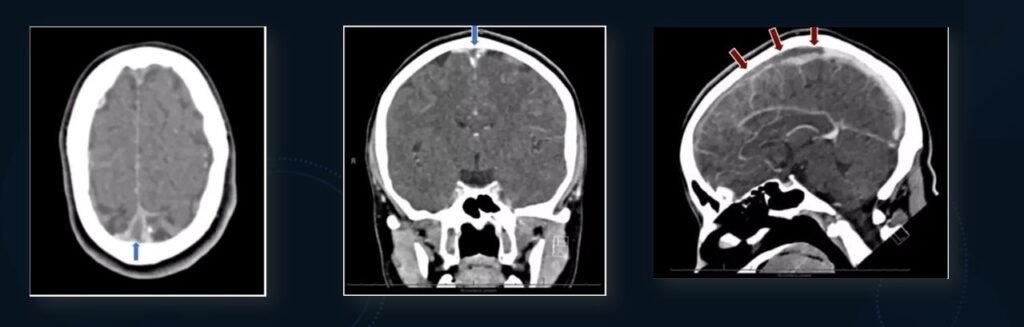

- Underwent non-contrasted head CT.

NCCT- Increased density in the anterior aspect of superior sagittal sinus and small frontal white matter haemorrhage

The area of hyperdensity corresponds to the location of superior sagittal sinus.

- CT SHOWS MIDLINE HYPERDENSITY CORRESPONDING TO LOCATION OF SUPERIOR SAGITTAL SINUS.

- CT VENOGRAM WAS ORDERED.

CT VENOGRAM: